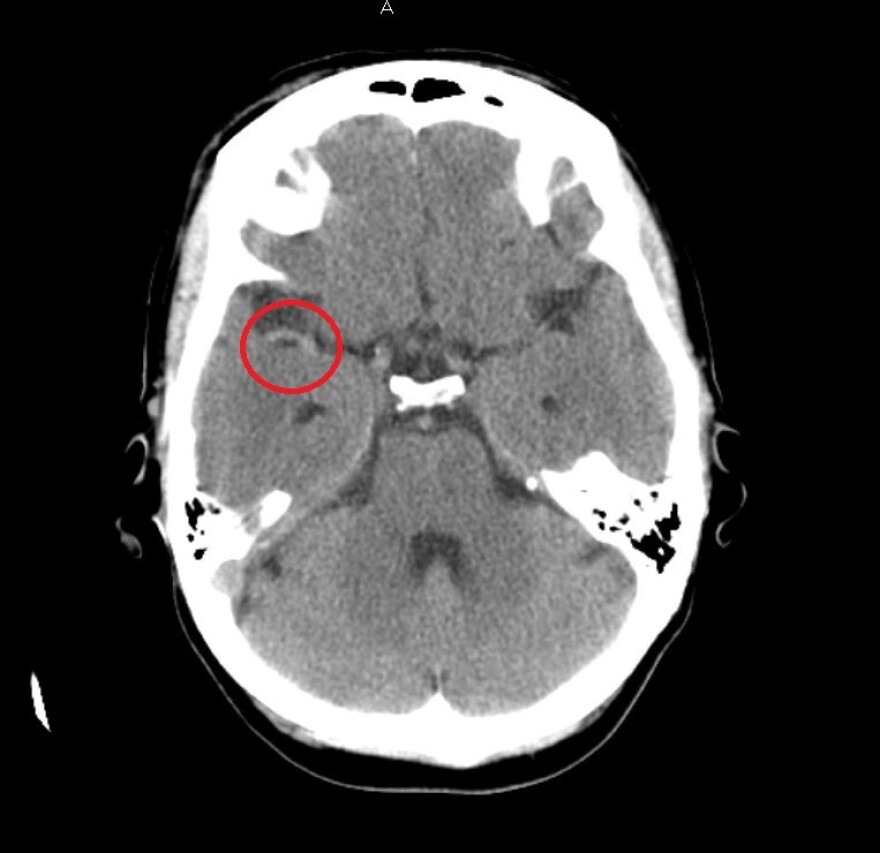

WHAT HAPPENS TO THE BRAIN DURING A STROKE

During a stroke, blood no longer reaches all areas of the brain. There are three types of strokes but the most common kind is an ischemic stroke, which occurs when a blood clot restricts blood flow to certain areas for the brain.

“The brain tissue is extremely dependent on blood supply,” said Dr. Alejandro Hornick. “So whenever blood stops reaching an area of the brain, the brain only has a few minutes that it can live without this, so the brain quickly starts dying.”

Any time spent reaching a stroke specialist cuts into a small window to deliver life-saving care. That includes a drug called TPA, which dissolves clots in the brain, or surgery to remove the clot.